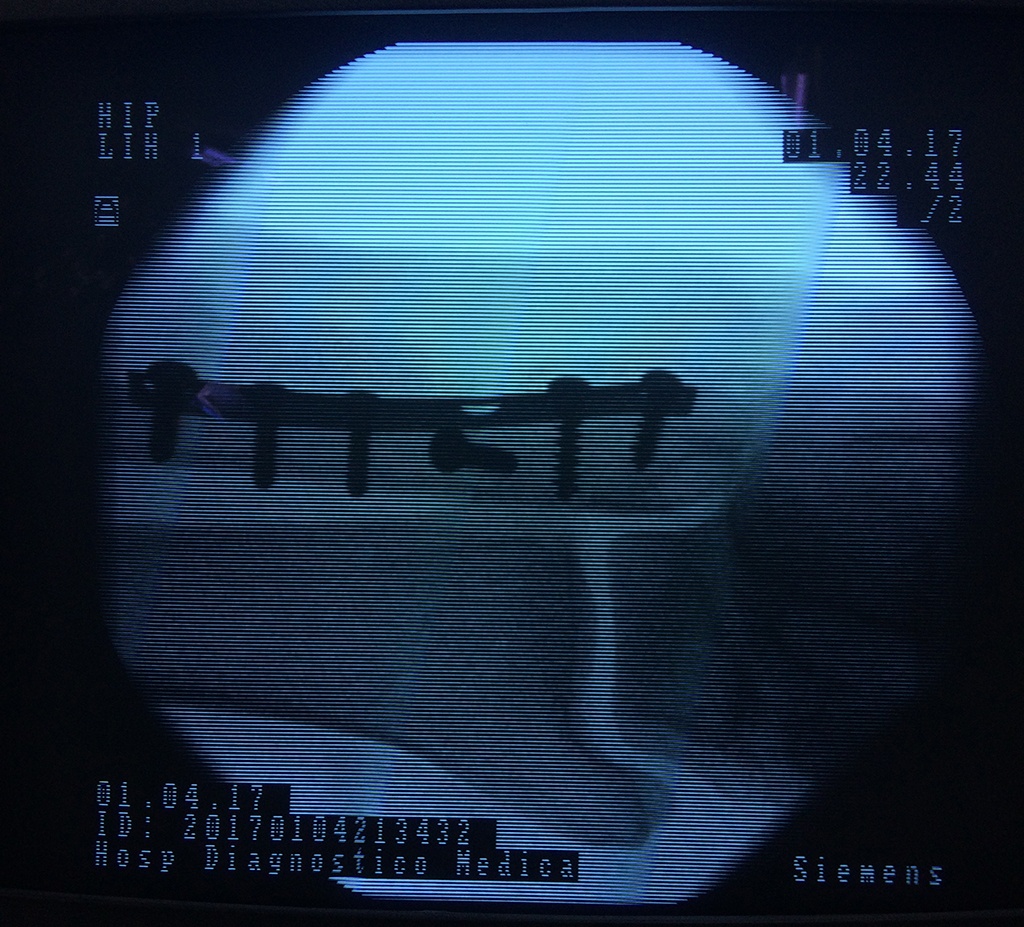

Cuando se necesita cirugía, es probable que esta implique el uso de clavijas de metal, tornillos o placas para sostener los huesos en su lugar mientras la fractura se consolida. Los elementos de soporte pueden ser temporales o permanentes.